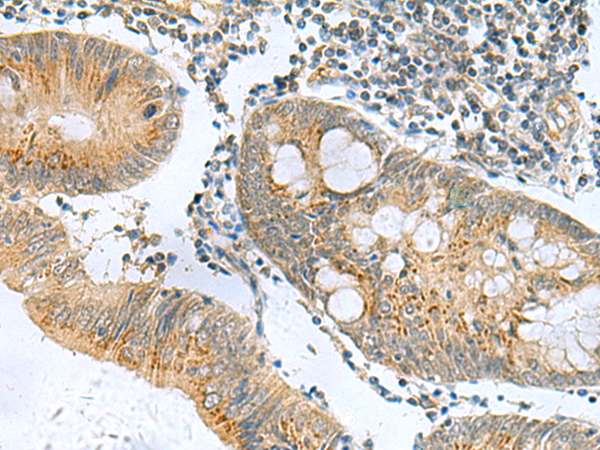

分类: 科研抗体货号: P10703别名: ARO; ARO1; CPV1; CYAR; CYP19; CYPXIX; P-450AROM应用: IHC反应种属: Human, Mouse, Rat